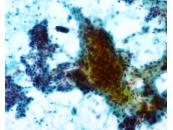

第37回日本臨床細胞学会九州連合会学会(佐賀)スライドカンファレンス症例3

種別:乳腺

出題:○山口 倫、阿部 英二.久留米大学医学部附属医療センター 病理診断科・臨床検査室

| 年齢 | 61歳 | 性別 | 女性 |

|---|---|---|---|

| 採取部位 | 右乳房C領域 | 採取方法 | FNA |

| 検体処理法 | 合わせ法 |

臨床所見

臨床診断:乳癌疑い

臨床経過:約2ヶ月前から、右乳房のしこりを自覚し来院。

触診上、右乳房C領域で、乳頭から約3cmの場所に、径1.5cm大の

硬い腫瘤を触知する。

| 正解 | 1.腺筋上皮腫 |

|---|

▼選択肢及び投票結果

| 1.腺筋上皮腫 | 29件 | (36.2%) | |

| 2.乳管内乳頭腫 | 6件 | (7.5%) | |

| 3.線維腺腫 | 7件 | (8.8%) | |

| 4.浸潤性乳管癌 | 15件 | (18.8%) | |

| 5.基質産生癌 | 23件 | (28.7%) | |

| 投票総数 | 80件 | (100%) |